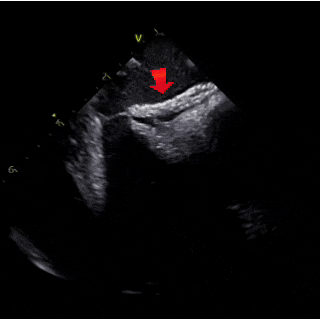

出院前评估

超声描述:

各房、室内径正常,主动脉窦部内径正常,升主动脉内径稍增宽。各瓣膜形态、回声及开放活动未见异常。左室壁厚度正常,静息状态下左室壁收缩运动未见明显异常。房间隔中部可见封堵器强回声,位置固定。室间隔回声未见中断。心包及心包腔未见异常。

CDFI:房间隔处未见房水平分流,二、三尖瓣房侧及主动脉瓣下可见少许反流束,测TV反流速度2.3m/s。二尖瓣口舒张期血流速度:E/A>1。组织多普勒显像(TDI):二尖瓣环E′/A′<1。

超声诊断:

卵圆孔未闭封堵术后:升主动脉稍增宽、主动脉瓣反流(轻度)、二尖瓣反流(轻度)、三尖瓣反流(轻度)、左室松弛性异常、左室收缩功能正常。